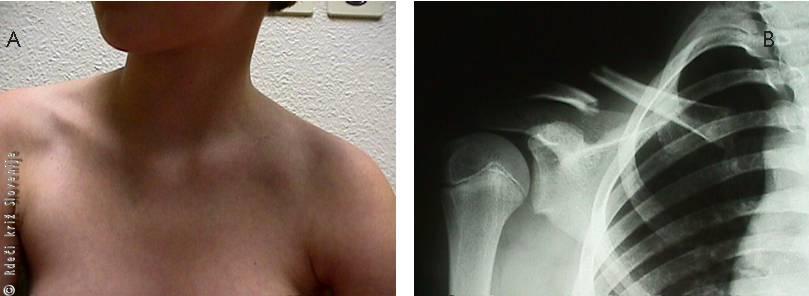

Slika 3

A – Zlom ključnice z oteklino in spremenjeno obliko, ki jo tipljemo kot stopničasto deformacijo.

B – Ramenski del zlomljene ključnice ponavadi leži globlje in nižje, kar vidimo na rentgenski sliki.